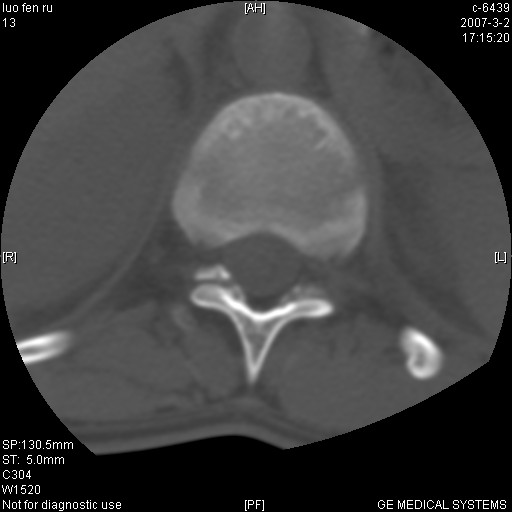

t11椎体前缘不规则形骨质破坏,周围有硬化边,软组织肿块不明显,首先考虑:骨嗜酸性肉芽肿 。期待随访结果。

病人病史不长,病变表现比较明显,如果是结核,病史不支持,椎间隙不窄,临近椎体正常,椎旁无冷浓疡,但从病变本身硬化也较多,均不太支持结核。慎重考虑的话,可以问一下病人有无结核病史。如果没有,更多的应该考虑陈旧性骨折,伴有慢性椎间盘炎可能。确诊后记着告知啊!

第一感觉就像嗜酸性肉芽肿,骨折及tb不能解释表现